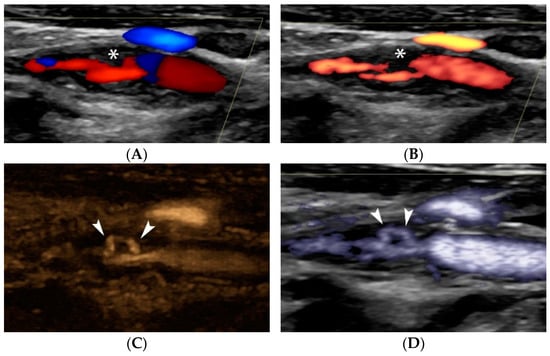

Figure 6.

“Handle-shaped” ulceration visualization on Doppler and non-Doppler techniques. Colour Doppler image (A) showing a moderately stenotic internal carotid artery plaque with irregular surface (asterisk). Power Doppler technique (B) confirming the findings but visualizing more pronounced irregularity (asterisk). B-Flow technique with (C) and without static tissue suppression (D) show that there is actually a tunnel-like ulceration (arrowheads), also partially identified on CTA (E) as an area of enhancement (arrowhead) inside the plaque. Note the blurred appearance of ulceration on CTA due to the lower spatial resolution of the technique as compared with ultrasound, which offers excellent spatial resolution in the field-of-view, particular in the near field.